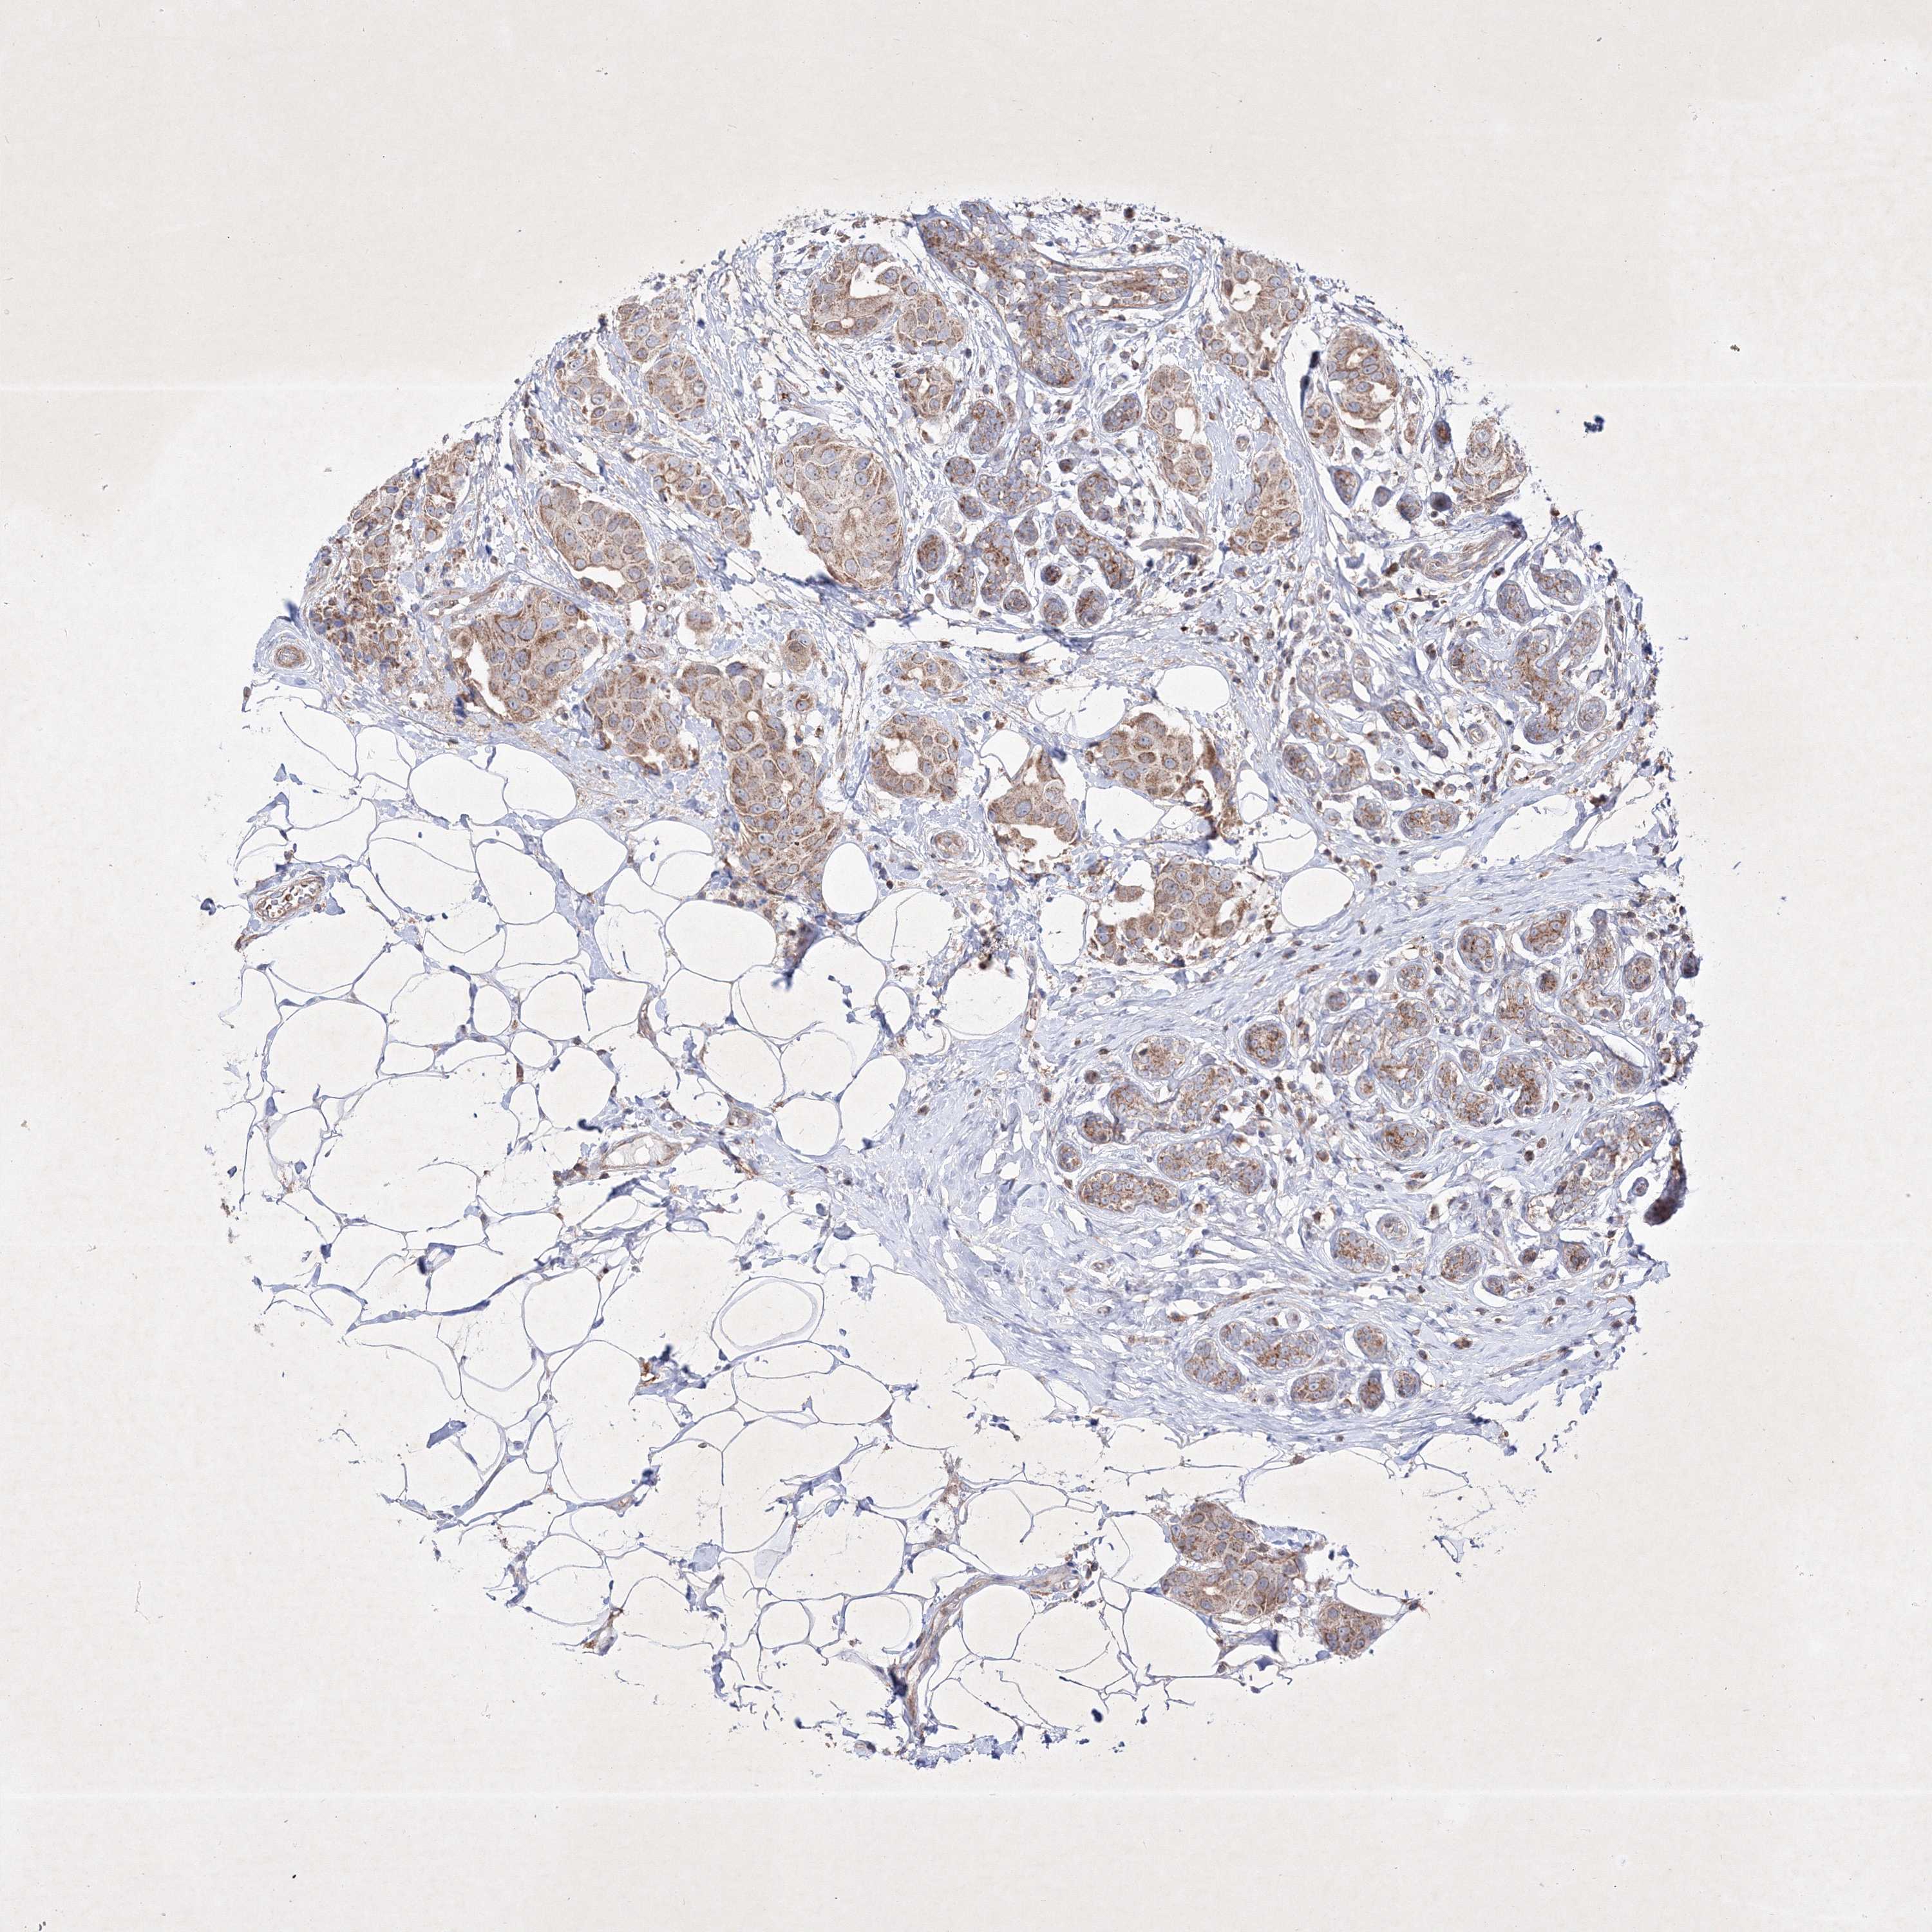

CANCER BREAST CANCER Show tissue menu

BRCA TCGA BRCA VALIDATION PROTEIN EXPRESSION